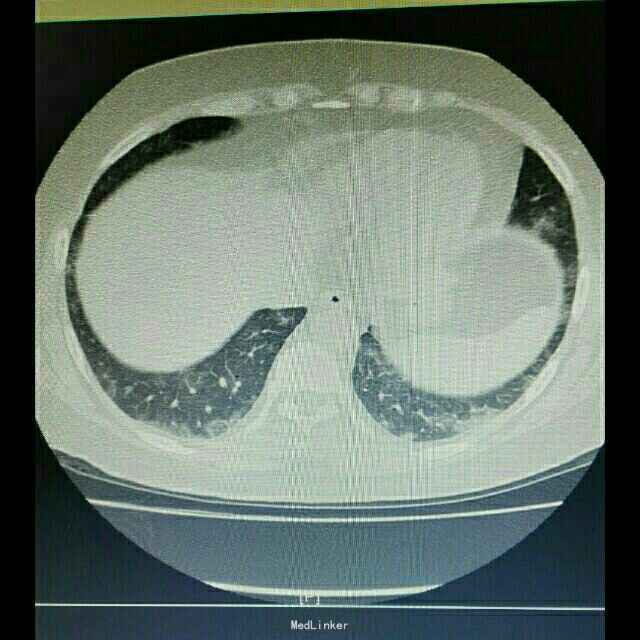

辅助检查:入院后行紧急胸部CT检查提示双肺弥漫性炎症改变,双下肺更加明显。

诊断:肺部感染,异体肾移植状态 治疗:根据胸部CT检查提示,真菌感染可能性大,给予科赛斯抗真菌治疗,加用舒普深抗细菌治疗。进一步检查生化、降钙素原、真菌D葡聚糖等炎性指标,监测患者体温、血气等指标。